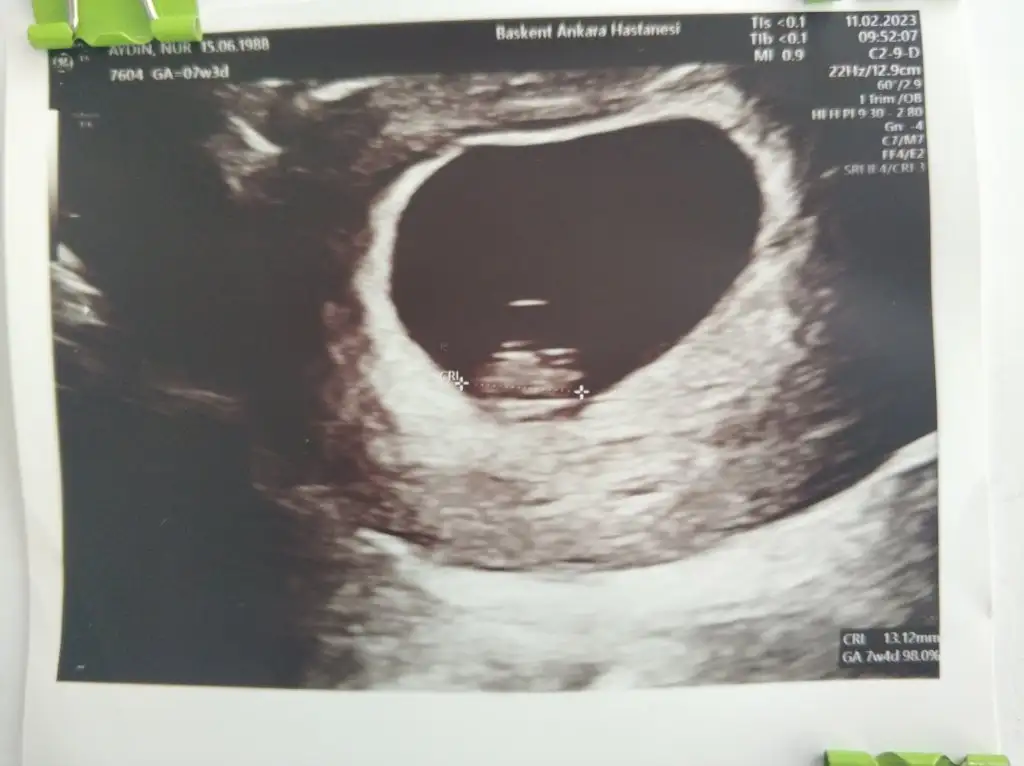

Ramziye gore erkek canım ama ilerleyen haftalarda netlesrbenimkide 7 haftalık karından ☺Eki Görüntüle 3200946

Bana da bakabilir misin lütfen 5+4 erken belki ama merakRamziye gore erkek canım ama ilerleyen haftalarda netlesr

Kızlar ultrason fotolarınızı atın 6 ve 7.hafta ya da 11. 12. 13. Hafta yorumlayayim. Amacım kesin bilmek değil net bi şey söyleyemem ancak ultrason net olursa daha iyi olur :)